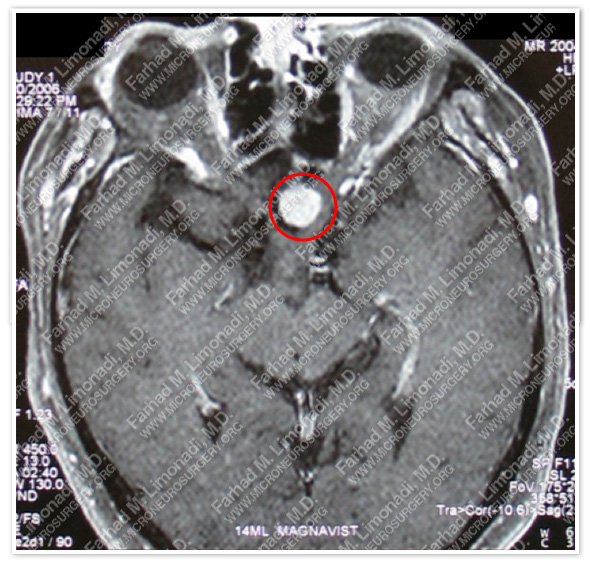

Imaging

MRI scan of the patient’s brain shows a dural based tumor in the suprasellar, or tuberrculum sellae.